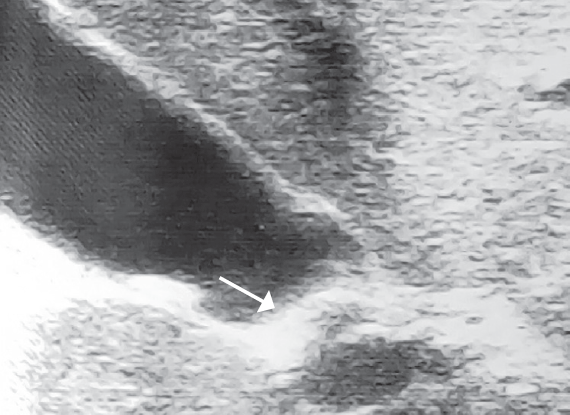

Результаты исследования. У всех пациентов с желчнокаменной болезнью выявлены различные варианты деформации в области пузырного протока. Одной из основных причин возникновения желчнокаменной болезни у детей являются изменения в области пузырного протока. Ни у одного пациента не было найдено конкрементов во внепеченочных желчных ходах. У пациентов с хроническим бескаменным холециститом патологии в области пузырного протока найдено не было.

Заключение. Одной из основных причин возникновения желчнокаменной болезни у детей являются изменения в области пузырного протока, что вероятнее всего приводит к затруднению оттока желчи из желчного пузыря, с последующим образованием конкрементов. Следовательно, проведение консервативного лечения при желчнокаменной болезни у детей представляется малоэффективным и методом выбора при лечении данной патологии может быть холецистэктомия.